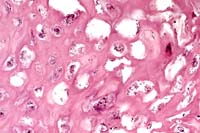

- Case 4-1. Liver. Large portal vein to right contains

sloughing cells with basophilic intranuclear inclusions. Similar

intranuclear inclusions are in most degenerating hepatocytes

as well.

- AFIP Diagnosis: Liver: Hepatocellular degeneration

and necrosis, diffuse, with mild multifocal acute hepatitis and

vasculitis, numerous hepatocellular intranuclear inclusion bodies,

and rare endothelial intranuclear inclusion bodies, striped skunk

(Mephitis mephitis), mustelid.